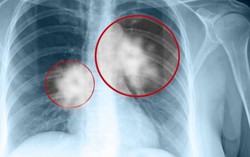

Phòng & chữa bệnh 13:00 05/09/2016NSƯT Hán Văn Tình (lão Quềnh) vừa ra đi vì ung thư phổi, nghệ sĩ Minh Thuận (Lâm caro) nguy kịch vì căn bệnh này. Trước đó, chị Đậu Thị Huyền Trâm, cũng tử vong sau khi từ chối điều trị ung thư phổi để cứu con. Ung thư phổi là gì mà nguy hiểm đến vậy?